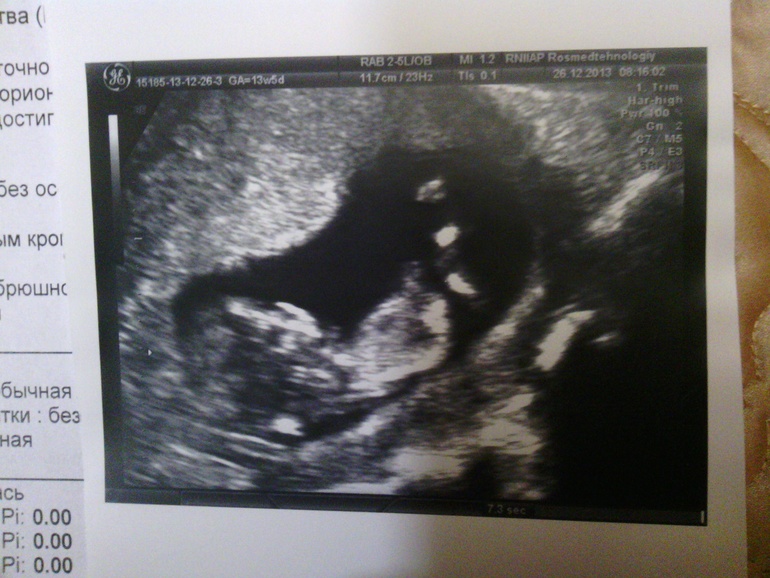

Девочки,срок 12-13 недель...как вы думаете,кто будет? Фоточки малышика ниже)

девочка 100 процентов. бугорок параллельно позвоночнику.если б мальчик то 30 градусов наклон был бы

Да я только о сыне и мечтаю)))) вот в 20 недель мне сказали что скорее всего девочка...то есть в 13 недель мальчик был,а в 20 девочкой стал...я так растерялась,что забыла фото попросить в 20 недель....я уверенна что мальчик, а они мне девочка)

какая деушка,видно же..кое что))причем если не на первой-там размыто-то четко се на 2 по-моему видно картинке)))